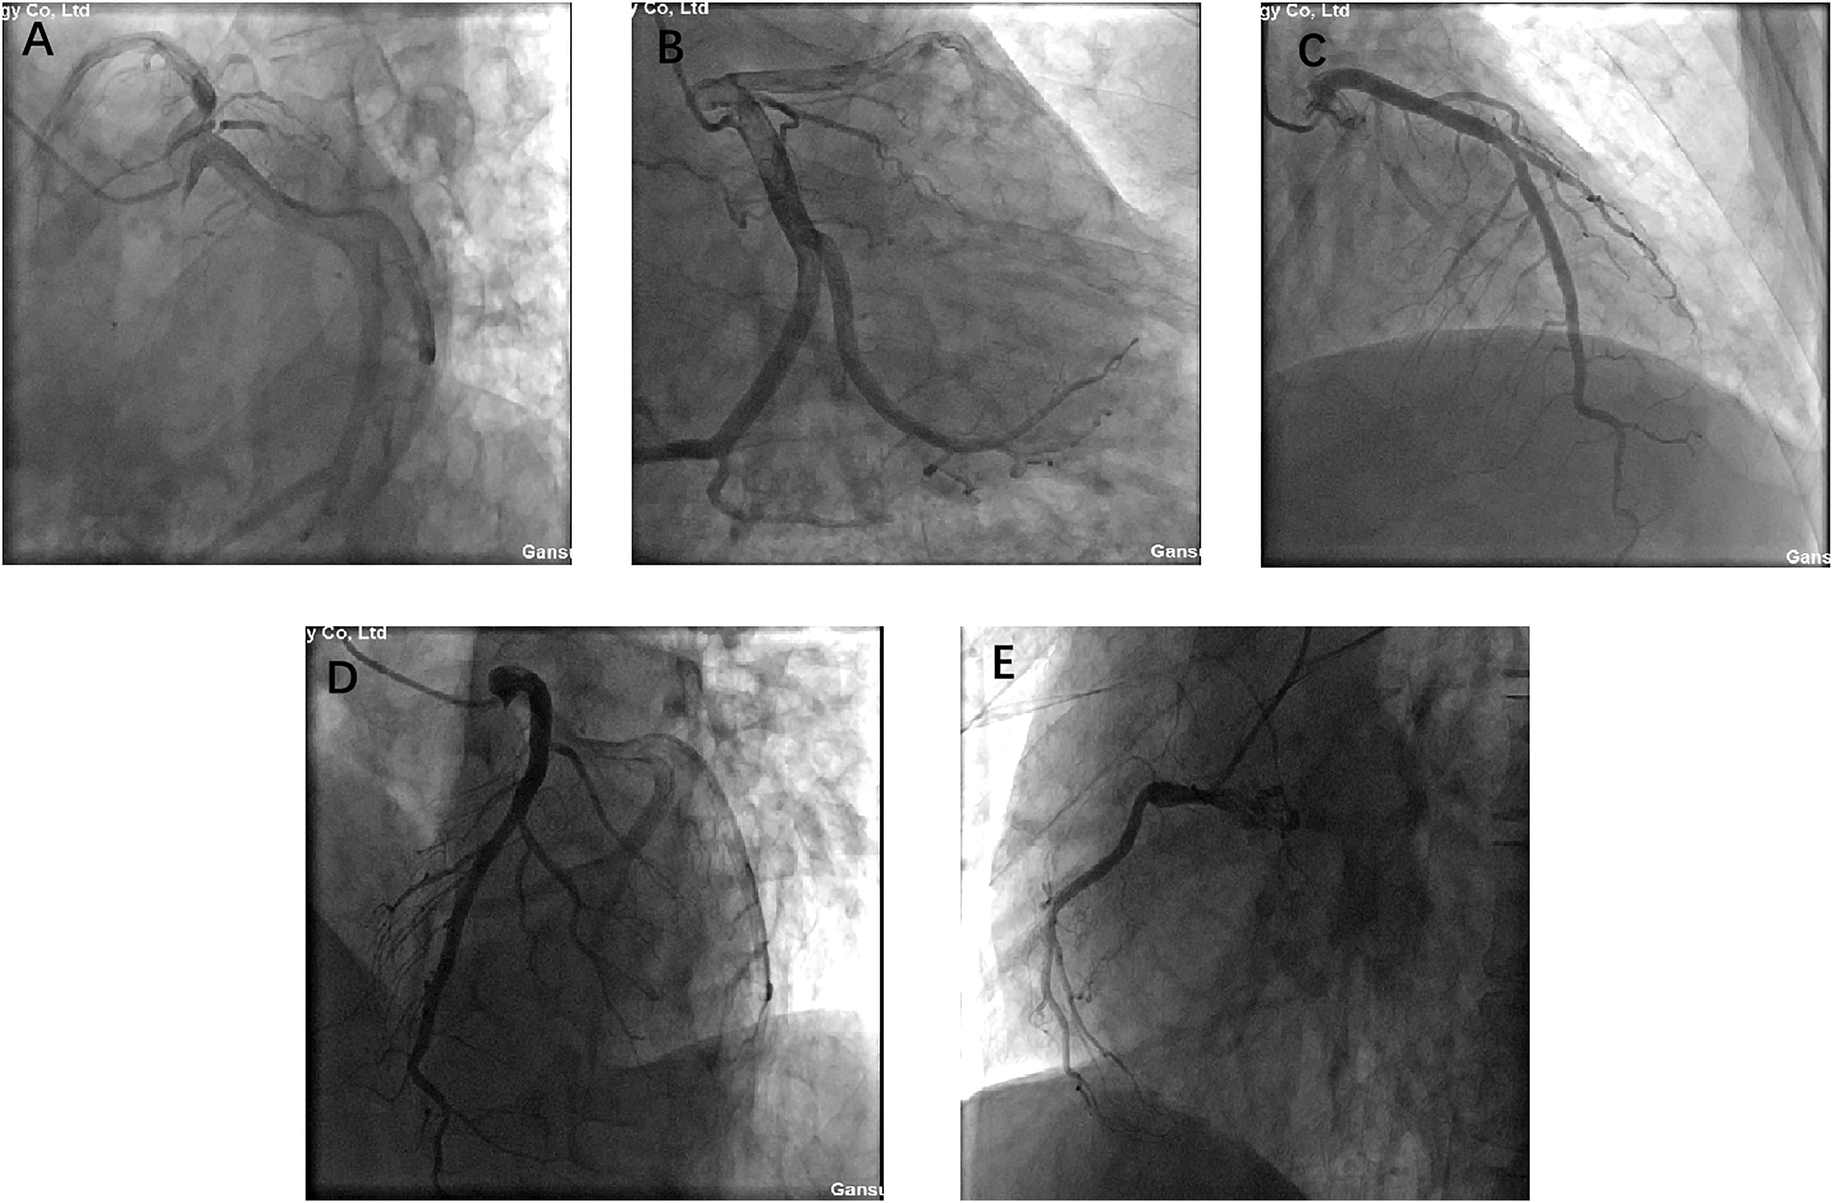

Prior to surgery, coronary angiography was performed due to the patient's age and risk factors. The angiogram demonstrated left main trunk dilation, mild plaques in the mid-left anterior descending artery, diffuse dilation of the circumflex artery, and a diminutive right coronary artery, but no significant coronary artery stenosis (Figure 2). These findings effectively excluded significant coronary artery disease preoperatively.

Figure 2

A, B, C, D, and E present coronary angiograms in different projections. The results indicate: dilation of the left main coronary artery, plaque in the mid-to-distal segment of the anterior descending branch, diffuse dilation of the circumflex artery, hypoplasia of the right coronary artery, no significant coronary stenosis, and normal blood flow.